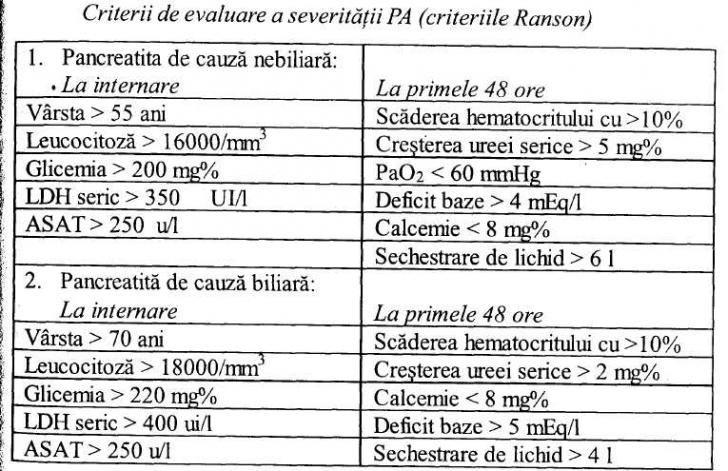

PANCREATITA ACUTA

PANCREATITA ACUTA DEFINITIE Pancreatita acuta (PA) este definita ca un tablou clinic instalat brusc caracterizat prin dureri abdominale, asociat obisnuit cu cresterea enzimelor pancreatice in sange si urina (datorita unui proces de autodiCiteste tot ... 3274 cuvinte

Dimensiune medie

+ cu poze |